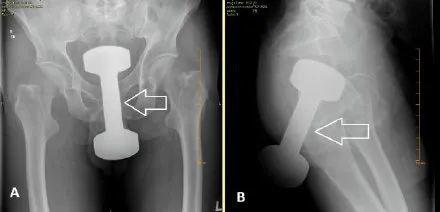

酒瓶、刀、叉子、喷雾罐、哑铃、灯泡、罗非鱼……只有你想不到的,没有“直男”们不敢塞的,比如说,哑铃。